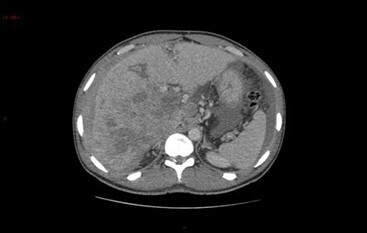

Le scanner ci-dessous est réalisé.

Le scanner abdomino-pelvien est réalisé en décubitus dorsal, non à jeun et en apnée inspiratoire.

Le volume d’examen couvre des coupoles diaphragmatiques jusqu’à la symphyse pubienne, déterminé par un topogramme frontal +/- sagittal.

L’acquisition sans injection permet la visualisation des calcifications, en situation d’urgence le sang « frais » (hématome récent), et surtout de calculer le différentiel de rehaussement pour mettre en évidence le rehaussement d’une lésion (pour, par exemple, différencier une masse tissulaire d’une masse kystique).

Le volume de produit de contraste iodé injecté est d’environ 2 cc/kg à raison d’un débit d’environ 2 à 3 mL/s.

Le temps artériel correspond à une acquisition à 25-35 secondes après l’injection et se caractérise par une opacification franche des structures artérielles +/- une parenchymographie débutante pour les temps artériels réalisés tardivement (vers 40 secondes, comme lors des bilans de cancers pancréatiques).

Le temps portal correspond à une acquisition à 70-80 secondes après l’injection et se caractérise « stricto sensu » par une opacification des vaisseaux portes. C’est le temps de la parenchymographie, ou les rehaussements des différents organes de la cavité abdominale sont étudiables. Les structures vasculaires artérielles et veineuses ont alors un rehaussement équivalent.

Le temps tardif correspondant à une acquisition à 3 minutes après l’injection, peut par exemple permettre une meilleure visualisation du lavage d’un CHC, ou bien, dans un contexte d’urgence avec recherche d’un saignement abdominal, de visualiser l’extravasation de produit de contraste sous forme de flaque hyperdense (« blush »). Il est à distinguer du temps tardif (10 minutes) réalisé dans les scanners rénaux ou uroscanners où l’objectif est la visualisation des voies excrétrices urinaires.